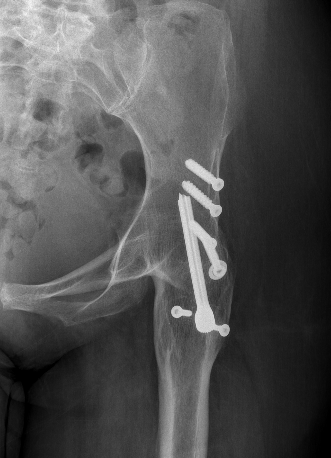

Exposure

- identify and protect sciatic nerve

- perform GT osteotomy / trochanteric slide

- may require adductor & psoas tenotomy

Neck osteotomy

- can be difficult to identify landmarks

- can damage acetabulum with saw